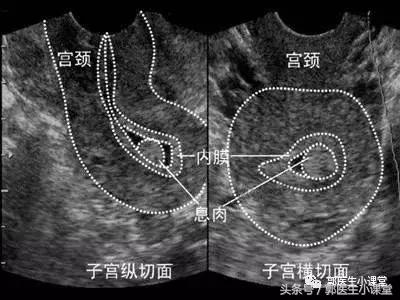

子宫内膜息肉在妇科算是比较常见的疾病,很多人可能平时没有任何不舒服的感觉,可能只是体检的时候做B超检查,结果B超报告就提示:子宫内膜增厚,不排除子宫内膜息肉可能,建议复查。

说到这里我要提醒一下大家,为什么我们一般建议大家体检的时候,选择月经干净后3-7天去做妇科B超。因为女性的子宫内膜厚度在月经的不同时间是呈周期性变化的,当月经前子宫内膜是最厚的时候,如果此时进行B超检查,会由于增厚的子宫内膜回声增强,影响对息肉的判断。这也是为什么有些人月经前做B超医生怀疑他有子宫内膜息肉,而月经干净后再复查就没事了的原因。

当然,这主要针对怀疑小的息肉,如果是1公分以上的息肉,基本还是可以分辨清楚的。

子宫内膜息肉是由子宫内膜局部过度增生所造成的,增生的内膜形成了一个或者多个凸向于子宫腔的肿物。这有点类似于宫颈息肉,只不过宫颈息肉是宫颈管部分的内膜组织增生,赘生物突出到了宫颈外而已。

子宫内膜息肉可以通过B超检查或者宫腔镜检查发现,一般采取手术治疗,不推荐药物治疗。